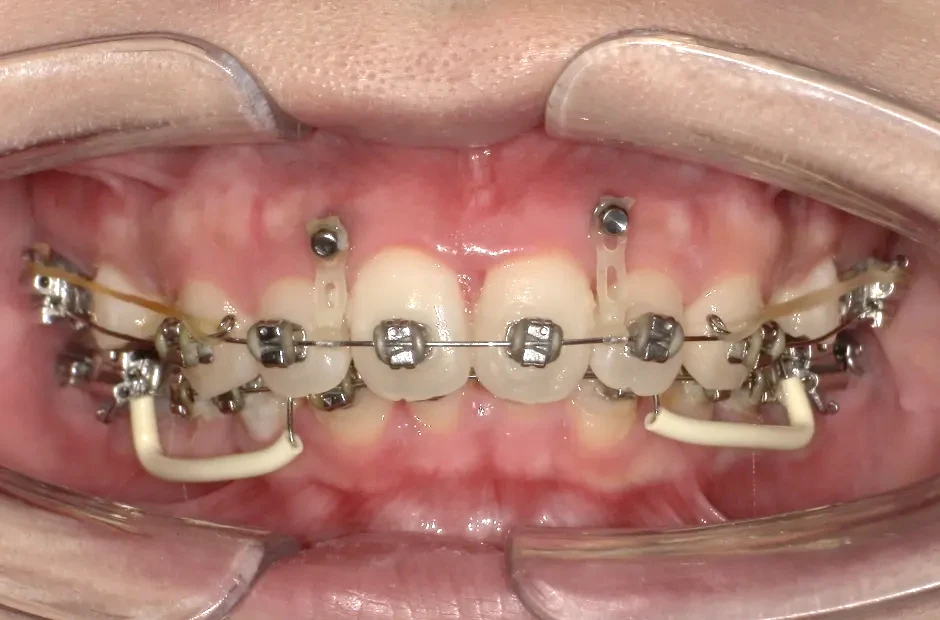

すきっ歯

| 診断名・主訴 | すきっ歯 |

|---|---|

| 年齢・性別 | 22歳・女性 |

| 治療期間・回数 | 2年半 30回 |

| 治療に用いた主な装置 | アンカー |

| 抜歯部位 | なし |

| 治療費 | 100万円(税抜) |

| リスク・副作用 | 装置による違和感・疼痛・歯肉退縮・歯根吸収・虫歯のリスクなど |

治療前

治療中

治療後